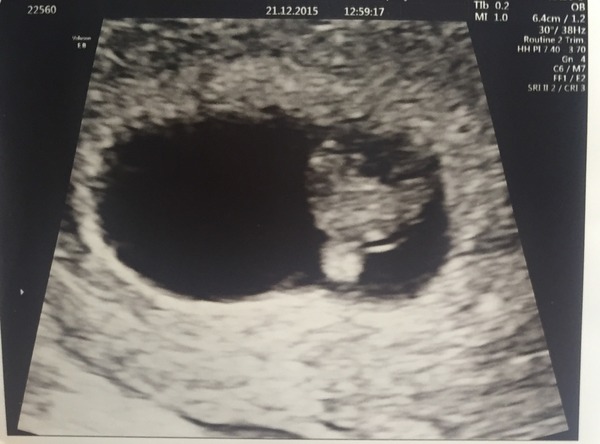

I am currently 10+6 and have my booking in appoint tomorrow with the midwife...no date yet for my scan! I had a 8 week private scan just before christmas and everything was showing fine, strong heartbeat and it was even moving around a little, nice to see (have included a little picture).

Congratulations huggy, lovely pic!